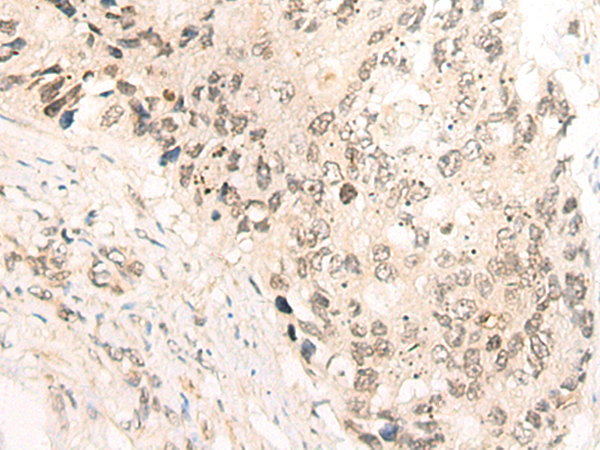

The image is immunohistochemistry of paraffin-embedded Human liver cancer tissue using 46944(CCNY Antibody) at dilution 1/35. (Original magnification: ?00)

The image is immunohistochemistry of paraffin-embedded Human colorectal cancer tissue using 46944(CCNY Antibody) at dilution 1/35. (Original magnification: ?00)